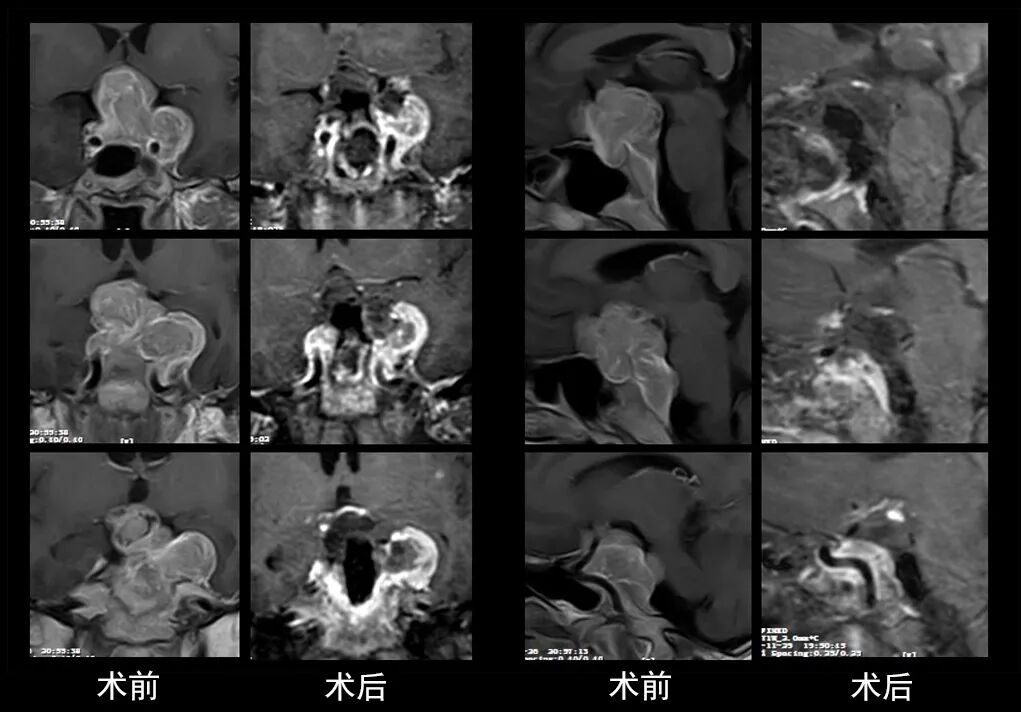

本研究中采用联合手术策略的代表性病例展示:

case 7

case 8